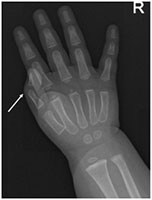

Baby Born with an Extra Thumb

Infant presented with an isolated congenital deformity of the right hand. A duplication of the thumb is seen clinically and radiographically.

Intra-op fluoroscopic image confirms the appropriate level of resection of the extra thumb.